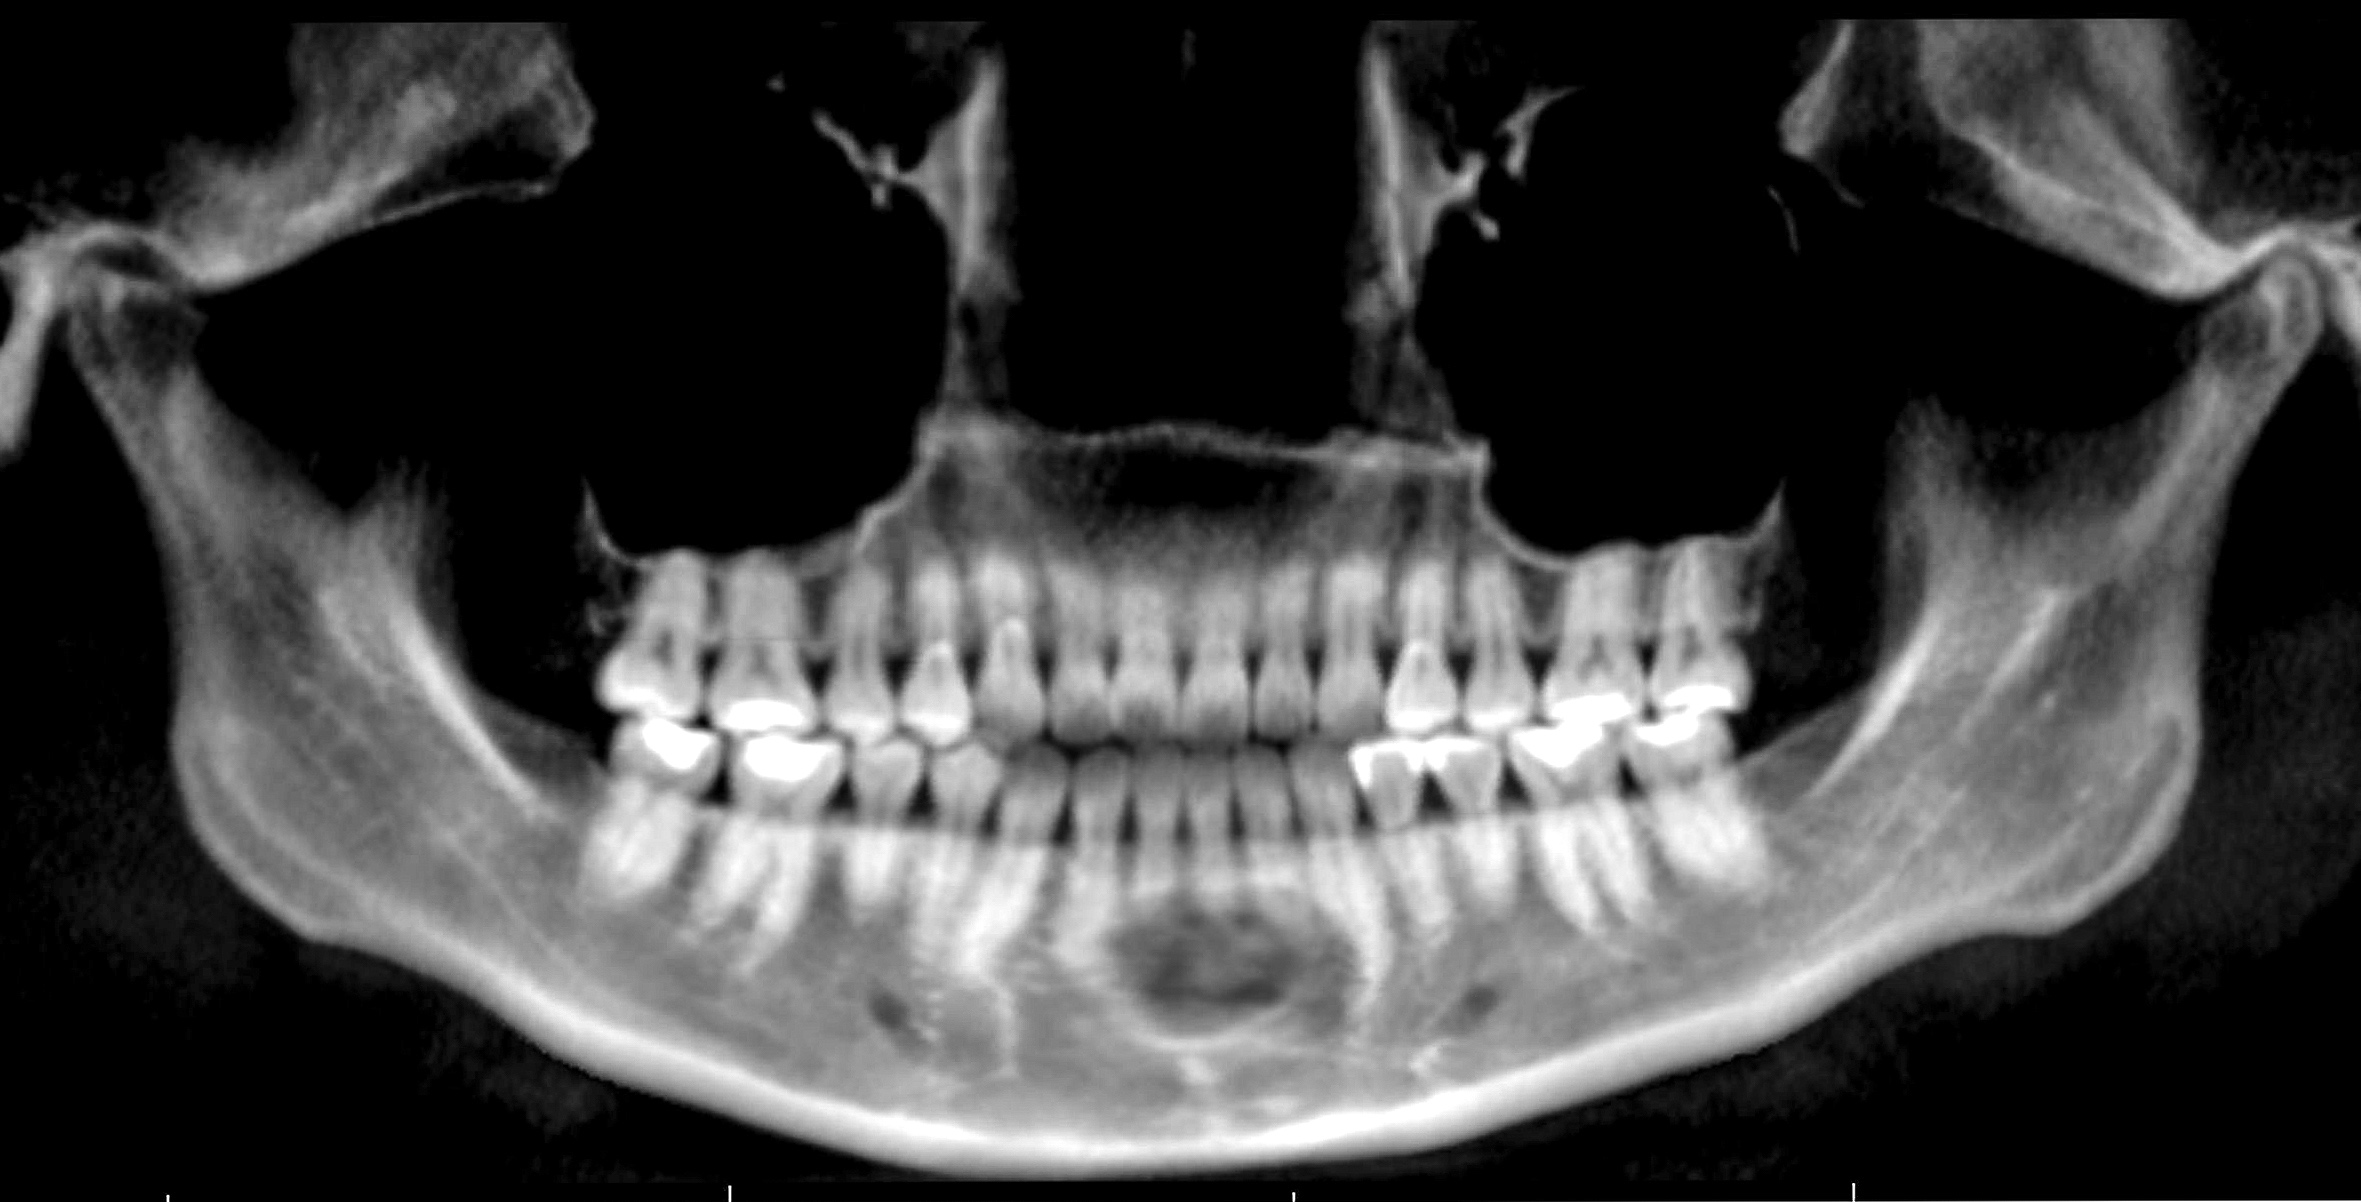

Radiology description

- Radiological findings vary according to maturity of lesion; early lesions show well defined corticated radiolucency and over time, lesion becomes progressively more radiopaque (Heliyon 2021;7:e07594, BMJ Case Rep 2020;13:e239286)

- Well circumscribed, unilocular lesion with centrifugal pattern of growth (Heliyon 2021;7:e07594)

- Can present as lesion with well defined sclerotic borders and is predominantly unilocular (BMJ Case Rep 2020;13:e239286)

- Larger lesions show expansion, thinning and perforation of buccal and lingual cortex and involvement of the lower border of mandible (BMJ Case Rep 2020;13:e239286)

Radiology images